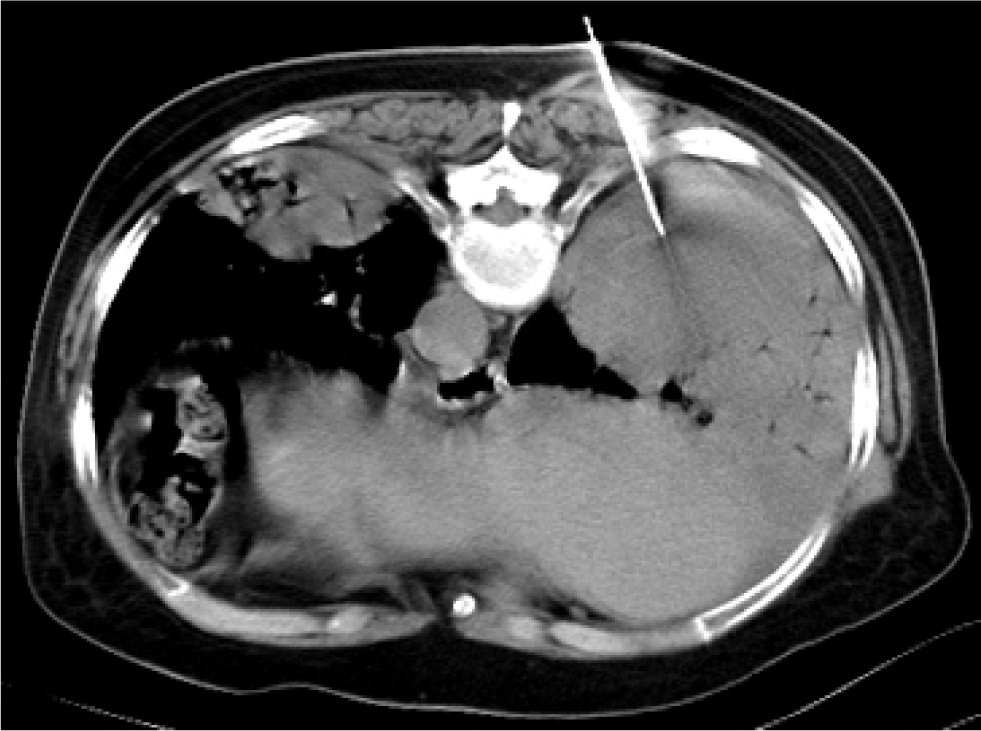

A 71-year-old female was taken to our hospital after experiencing bilateral chest pain and dyspnea for 20 days. She had no other complaints, such as fever, cough and bloody sputum. The patient had a history of arthritis pauperum for 20 years, and denied traditional Chinese medicines for treatment. She had no personal history of smoking and family history of cancer. On clinical examination, no palpable lymph nodes and hepatosplenomegaly were found. There was no obvious rale in bilateral lungs. Computed tomography (CT) of the chest demonstrated a high density shadow in the right middle lower lobe and left lower lobe, and air bronchogram was obvious (Figure 1 C). Bilateral hilar masses exits (Figure 1 E) and low density area was visible (green arrow). Mediastinal lymph nodes enlarged. The crescent shaped liquid density was in right pleura (Figure 1 D). CT of abdomen showed no abnormalities. Bone marrow biopsy showed no infiltration. CT-guided transthoracic core needle biopsy was performed (Figure 2). Pathological section demonstrated diffuse large B cell infiltration in small fibrous tissue. Immunohistochemical staining showed Mum-1(-), Ki-67 index 70%, Cyclin D1(-), CD43(+), CD5(+), Bcl-2(-), CD3(-), CD79a(+), CD23(-), CD10(-), Bcl-6(-), Syn(-), CD20(++), CD56(-) (Figure 3). Based on these findings, PPDLBCL was diagnosed. Due to personal reasons, the patient underwent cyclophosphamide pirarubicin vindesine dexamethasone (CHOP) chemotherapy without rituximab, which was planned to be repeated every 21 days for 6 cycles. Following the administration of 6 cycles of CHOP chemotherapy, chest pain and dyspnea were alleviated. Nevertheless, CT demonstrated bilateral masses and consolidation partially diminished (Figure 4 E F), while a new mass emerged in the right upper lobe (Figure 4 A D blue arrow). Unfortunately, at 9 months of follow-up, the patient died.

Computed tomography guided transthoracic core needle. Puncture needle is in the consolidation area of right lower lobe.